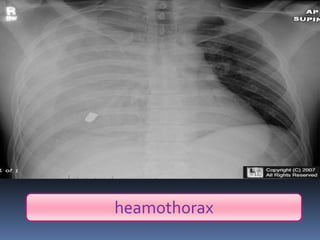

Abnormal Findings

Un equality of chest movement

Dullness on percussion

Decrease air entry

Tachypenic

heamothorax

chest tube